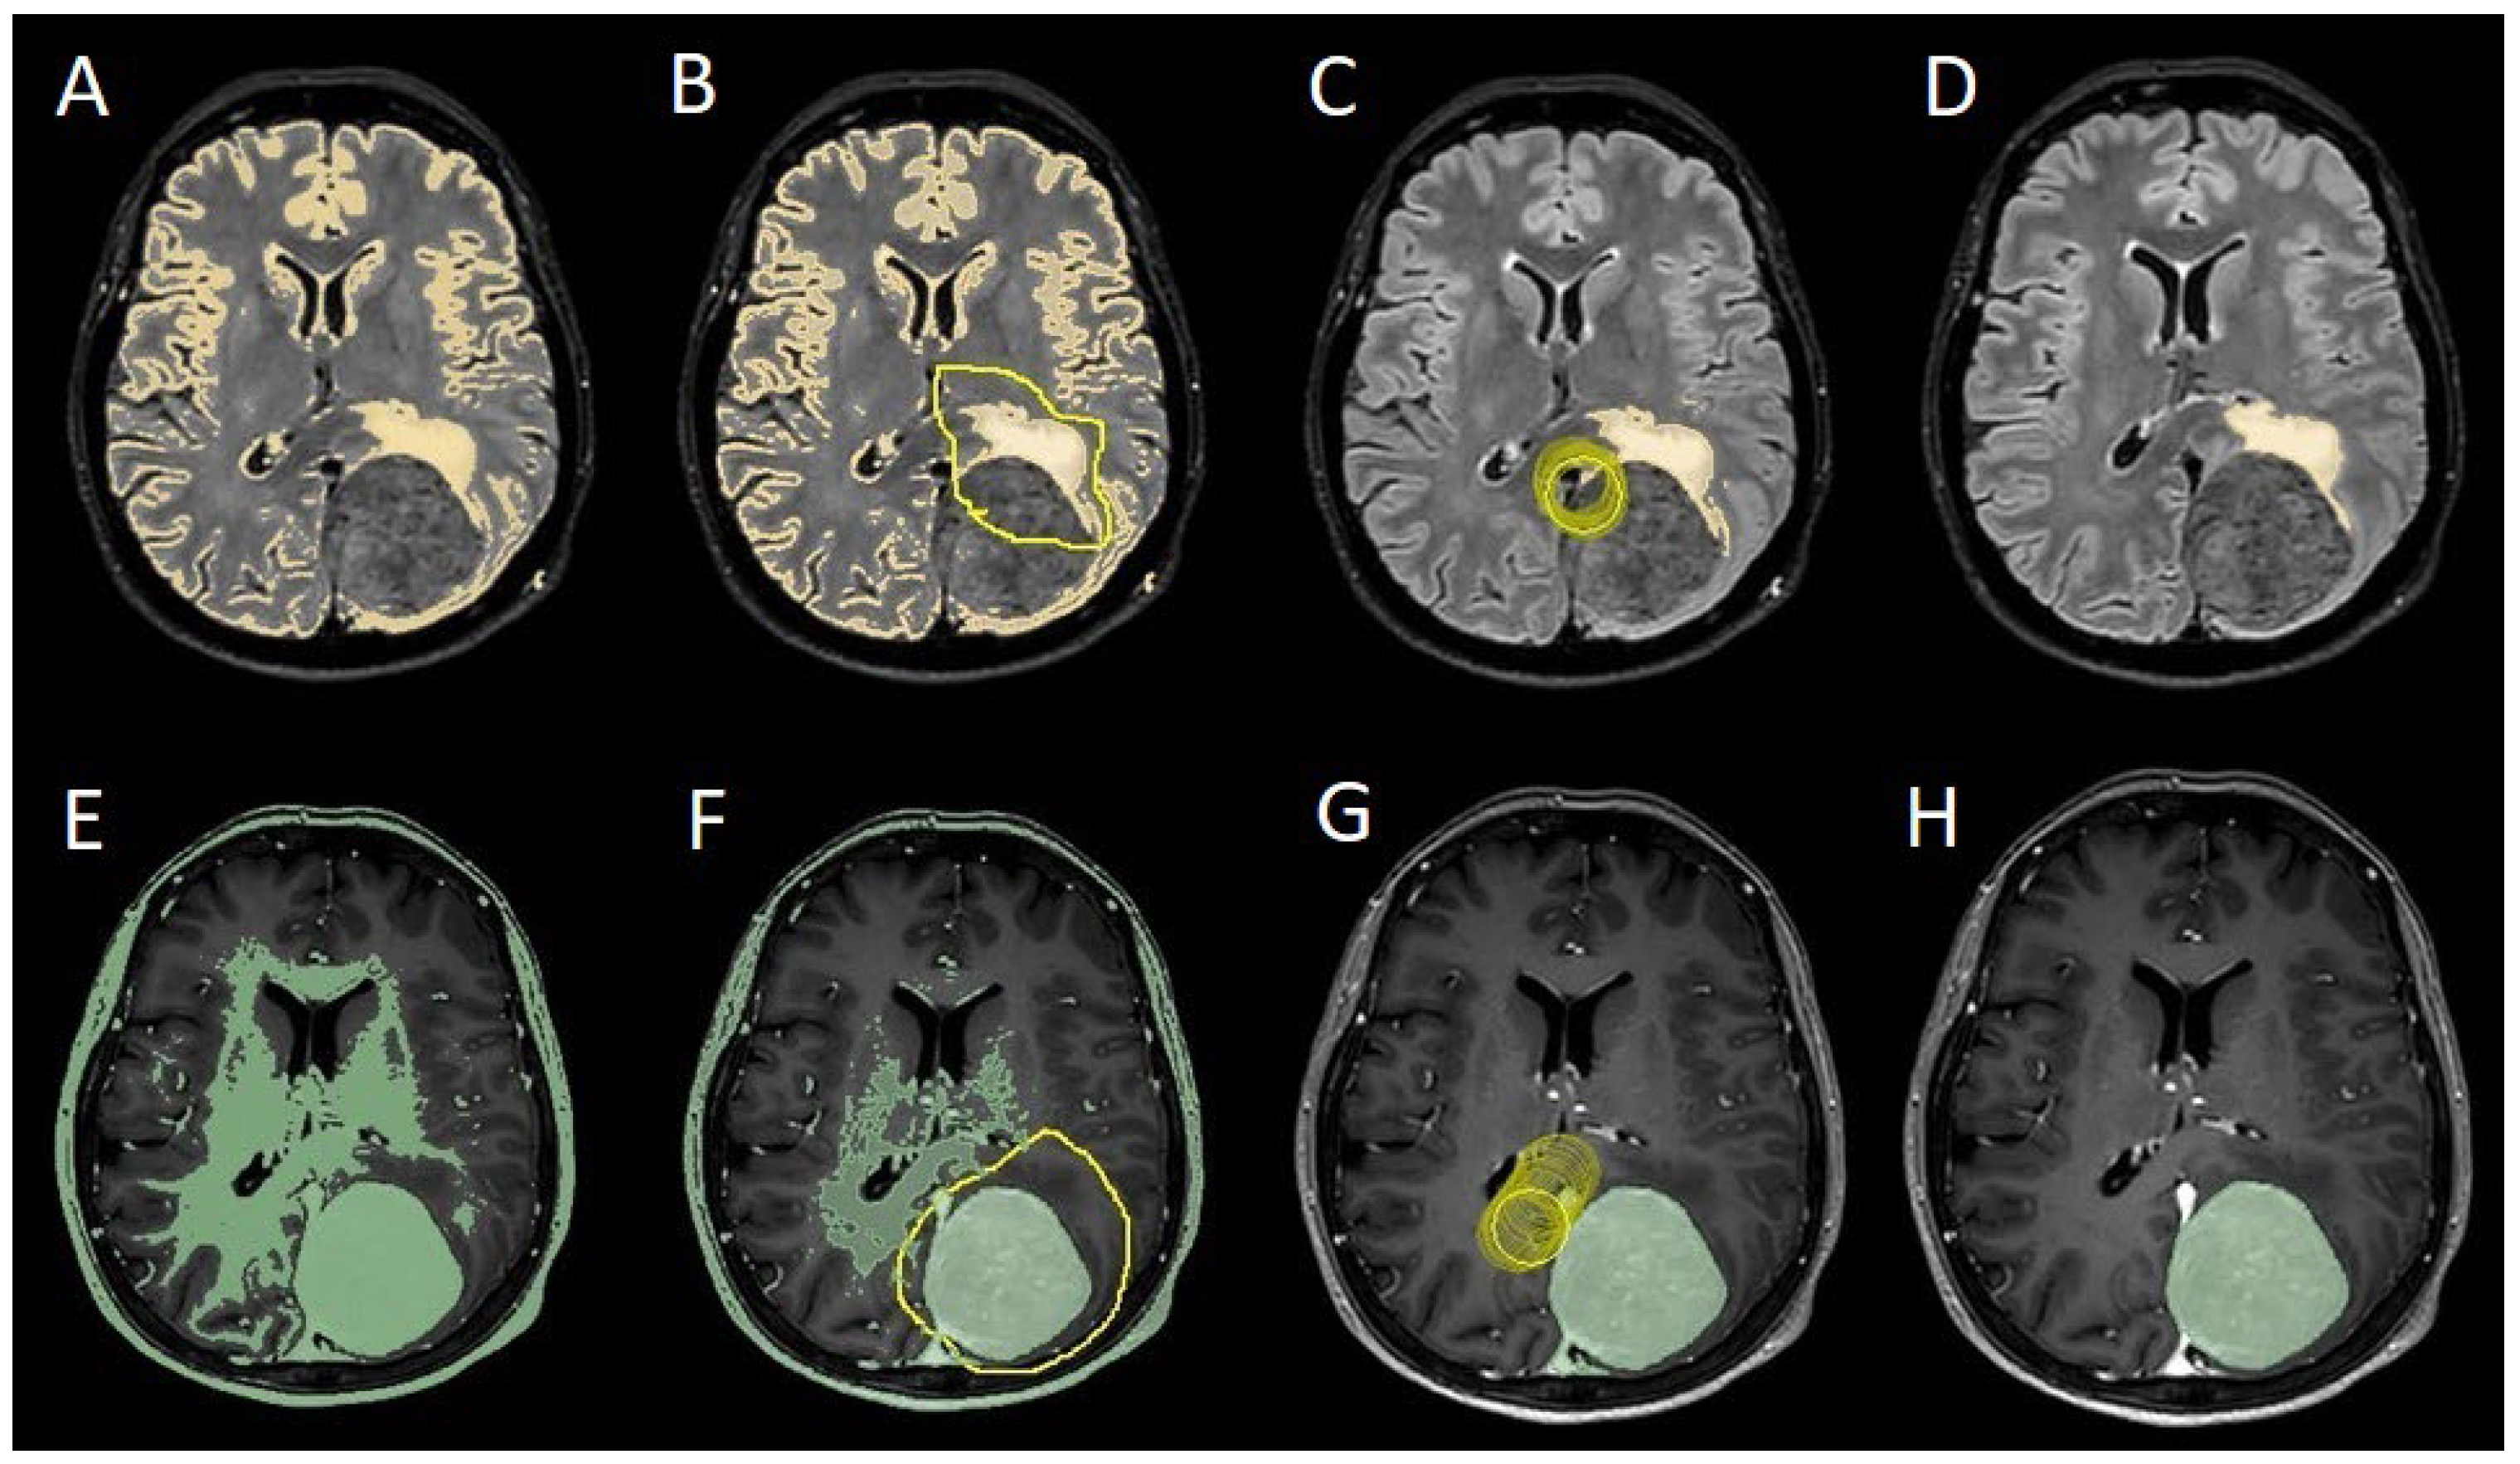

The patients underwent magnetic resonance imaging (MRI) at our Center using a 1.5T or 3T Tesla MRI machine (Ingenia 3T, Philips Medical Systems, Best, The Netherlands) with the standard oncological protocol [7]. Specifically for analysis, the sequences collected were T1-weighted with contrast enhancement to estimate tumor volume and conformation and FLAIR (Fluid-Attenuated Inversion Recovery) to quantify PE (Figure 1). We manage the preoperative imaging in DICOM (Digital Imaging and Communications in Medicine) format. The images from the T1-weighted with contrast enhancement and FLAIR sequences in DICOM format were processed through the Slicer website [12]. Tumor and PE segmentation was performed using a voxel-based analysis that integrated automated and manual methods (Figure 2). The process begins with an automatic thresholding technique to identify initial regions of interest based on intensity values (Figure 2A, 2E). This is followed by manual refinement to enhance accuracy and delineate precise boundaries (Figure 2B, 2C, 2F, 2G). The final segmentation provides volumetric measurements for both the tumor and the PE, aiding in quantitative analysis (Figure 3). The included patients' pre- and post-treatment clinical data were retrospectively extracted from our Center's computerized database. Collected data included demographic information, preoperative clinical details (presence or absence of epilepsy, onset symptoms, ASM therapy and number of ASMs taken, radiological characteristics of the meningioma), and postoperative data (Engel class [10], persistence or discontinuation of ASMs, ASM discontinuation timing, and possible postoperative functional deficits). A single examiner conducted data collection to minimize subjective variability in assessments. Surgical procedures were performed using a transcranial approach under general anesthesia. We excluded cases of surgical resection performed via an endoscopic endonasal approach. Cases of postoperative death (within one year after surgery) were excluded. Cases of WHO grade III meningiomas were excluded. The extent of resection (EOR) was determined based on the postoperative MRI (usually one month after surgery) and classified according to the Simpson grading system [22]. The study included cases of complete macroscopic meningioma resection (Simpson I-II-III). Cases with residual tumor persistence or recurrence after surgery (Simpson IV-V) were excluded (Figure 4). Measurement quantitative data were expressed as mean ± standard deviation (SD). We analyzed qualitative variables by summarizing them as frequencies and percentages, and relationships between variables were assessed using Fisher's exact test and the Chi-square test. Analysis of variance (ANOVA) or "N-1" Chi-squared test was used to assess statistical differences between the two groups or percentages. A p-value < 0.05 was considered statistically significant. ORs and RRs were calculated to assess the statistical significance of associations. ORs were used to measure the strength of association between categorical variables, while RRs were calculated to estimate the risk of an event in one group compared to another. These methods were chosen to assess the significance of relationships between the analyzed variables accurately.

Figure 2. Example of segmentation process with Slices website: A, E: automatic thresholding technique to identify initial regions of interest based on intensity values, respectively, for the PE on FLAIR sequence and the meningioma on T1-weighted with gadolinium sequence; B, F: partially automatic erase of redundant signal with "erase outside" tool; C, G: definition of boundaries of edema and tumor through manual erasement; D, H: final segmented volumes. FLARI: Fluid-Attenuated Inversion Recovery, PE: peritumoral edema.